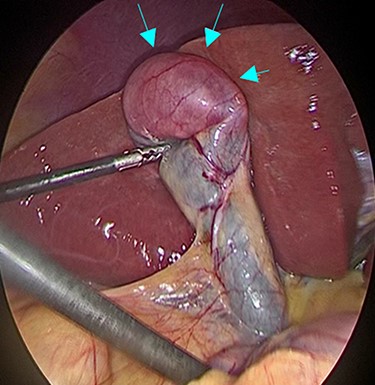

A 53-year-old man with history of liposarcoma had gallbladder tumor detected during routine ultrasonography (Fig. 1A) and was referred to us. He was first diagnosed as leg liposarcoma 5 years before and underwent complete resection. Despite of history of liposarcoma in his leg, he never developed any abdominal symptoms. Laboratory tests were unremarkable including carcinoembryonic antigen and carbohydrate antigen 19-9 (CA19-9) within their normal limits. Computed tomography (CT) scan demonstrated slightly enhanced 4-cm tumor located at gallbladder fundus (Fig. 1B). On magnetic resonance imaging (MRI), the tumor had high signal in both of T2 and diffusion weighed image and low signal in both of T1 and apparent diffusion coefficient (Fig. 1C–F). Based on these findings in imaging studies, our working differential diagnosis included liposarcoma and hemangioma rather than adenocarcinoma, and we recommended laparoscopic cholecystectomy. In the exploration, the tumor in the fundus appeared without serosal invasion (Fig. 2). Intraoperative ultrasonography revealed the tumor was contained in the gallbladder without infiltration into the liver, and in fact there was a distance between the liver bed and the tumor. Sonazoid enhanced ultrasonography ruled out liver metastasis and thus, we proceeded to laparoscopic cholecystectomy as planned. When the gallbladder was opened, yellowish white tumor was confirmed in the submucosal layer with the overlying mucosa intact (Fig. 3A). Histopathological examination revealed, this tumor as myxoid liposarcoma consisting of lipoblasts and round cells. There was no necrosis and proliferations of spindle and round cell component were identified in the background of myxoid stroma (Fig. 3B). These histological features were similar to the ones for the sarcoma in his leg that was resected before. The patient’s postoperative course was uncomplicated and was discharged home on Day 3. The adjuvant therapy was elected not to be given and he was placed on imaging surveillance with CT scan in every 3–6 months. In 16 months after this operation, he developed disease recurrence in the left popliteal fossa. There was no recurrence to date in the abdominal cavity at 28 months after the operation, he was alive with disease.

Intraoperative findings during laparoscopic cholecystectomy; The tumor was at fundus of gallbladder without serosal invasion.